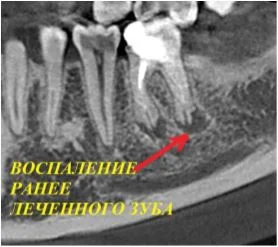

Давайте сравним снимки зубов, сделанные при помощи визиографа (слева), и при помощи компьютерной томографии (справа).

Как говорится, ощутите разницу. КТ - гораздо более точная и своевременная диагностика.

Воссоздавая орган (зуб) или даже совокупность органов, необходимо предельно точно знать исходную ситуацию. Корни зубов, каналы зубов, крупные сосудисто-нервные пучки, идущие внутри костной ткани, верхнечелюстная пазуха во всех подробностях и т.д. - в неискаженном виде все это можно увидеть только на компьютерной томограмме. Стоит ли говорить, что все эти структуры важны для имплантации, так как могут быть легко поврежденфы в ходе операции.